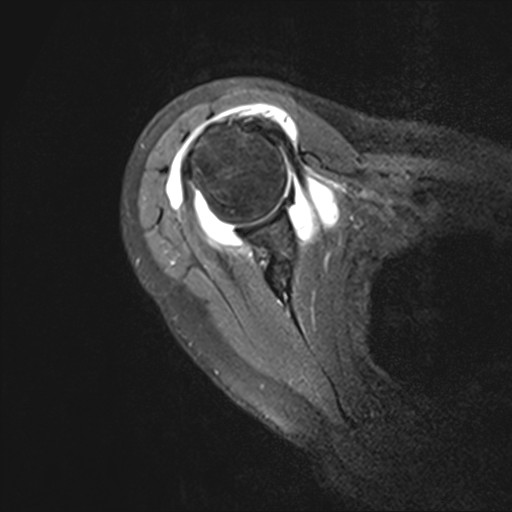

Rotatorenmanschettenriß in der Kernspintomographie

Der Patient berichtet, dass er beim Volleyballspiel beim Überkopfaufschlag eine Schultergelenksverrenkung (Luxation) erlitten habe. Er habe bereits zuvor leichte Beschwerden gehabt. In der Kernspintomographie zeigte sich ein Sehnenabriss an der Supraspinatussehne wie auch eine Kapselverletzung am vorderen unteren Gelenk. Arthroskopisches Vorgehen mit Rekonstruktion der Läsionen. Der Patient demonstriert nach 6 Monaten im Januar 2022 eine stabile Schulter im Rahmen der Liegestütze. Eine Wiederaufnahme des Volleyballspielens ist im Weiteren geplant.

62-jährige Patientin mit erheblichen Schmerzen und vollschichtiger Supraspinatussehnenablösung. Die Sehne war sehr weit zurückgezogen, bereits sichtbar auf der präoperativen Kernspintomographie und ließ sich auch intraoperativ nicht so weit mobilisieren. Eine Rekonstruktion war spannungsarm nicht möglich. Es wurde ein mit Flüssigkeit gefüllter Ballon unter dem Schulterdach arthroskopisch gestützt eingeschoben und entfaltet. Dieser Ballon führt neben einer Abstandshaltung zum Schulterdach zu einer Fremdköperreaktion und Membranbildung. Durch die anhaltende Trainingstherapie konnte die Patientin trotz des Defektes eine Rezentrierung des Gelenkes mit sehr guter anhaltender Funktion erzielen.

Infraspinatus und Subscapularis intakt

Supraspinatusdefekt